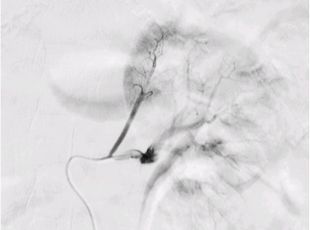

必要に応じてMRI検査や血管造影検査(左右の副腎静脈からホルモンサンプリング)を追加して総合的に診断します。